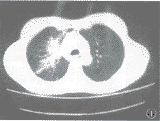

胸片示右肺门增大,上野见斑片状模糊阴影。CT扫描见:右肺上叶不规则斑片状病灶,有毛刺及纤维条索(图1)。小脑上蚓部见一边界清楚的低密度灶,无水肿区,右额顶叶见一大片状低密度区,其内见弧带状出血灶,右侧脑室略受压变形,右枕叶和左额叶各见一小圆形低密度灶。1个月后再次CT检查:颅内病灶仍存在,病灶囊变,右额顶叶病灶内出血影消失,病灶增强后不强化。5个月后胸片检查,右肺病灶消失;颅脑磁共振检查示原囊性灶仍存在,皮质下区及脑深部见多个小病灶(图2)。8个月时CT平扫:不见囊性灶,脑实质内见多发大小不一略高密度结节性病灶,占位不明显,以小脑半球居多(图3)。

图1 CT扫描,示右肺上叶不规则斑片状病灶,有毛刺及纤维条索